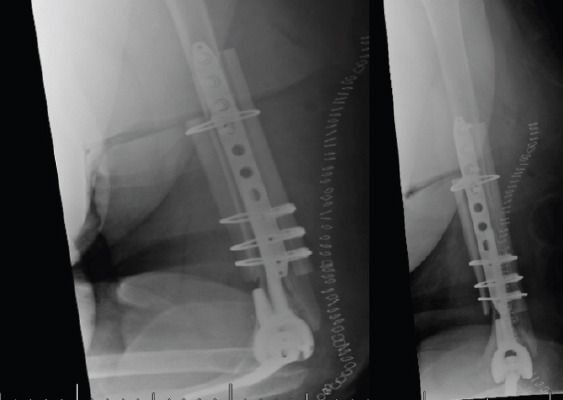

Case report: We present two cases of periprosthetic humerus fractures without implant loosening multiple years after the index procedures. They were treated with open reduction internal fixation (ORIF) utilizing a plate with medial and lateral cortical strut femoral allografting with implant retention.

Conclusion: Two cases of periprosthetic humerus fractures about total elbow arthroplasties were successfully treated with ORIF with medial and lateral cortical strut augmentation. Treatment for periprosthetic elbow fractures should be tailored to each patient based on factors, such as stability of implant, bone stock, and patient goals.